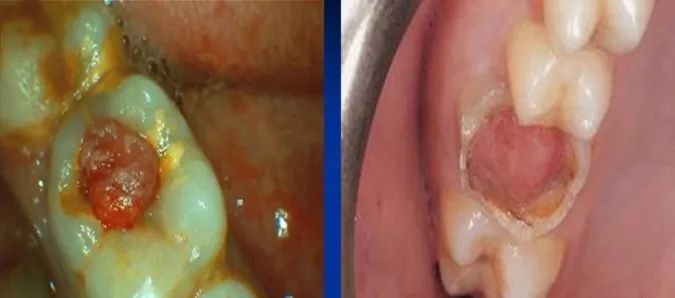

当查及患牙深洞有息肉时,临床上还要与牙龈息肉和牙周膜息肉相鉴别。牙龈息肉多是牙龈乳头向龋洞增生所致。牙周膜息肉发生于多根牙的龋损发展过程中,不但髓腔被穿通,而且髓室底亦遭到破坏,外界刺激使根分叉处的牙周膜反应性增生,息肉状肉芽组织穿过髓底穿孔处进入髓腔,外观极像牙髓息肉。在临床上进行鉴别时,可用探针探察息肉的蒂部以判断息肉的来源。当怀疑是牙龈息肉时,可自底部将其切除,见出血部位在患牙邻面龋洞龈壁外侧的龈乳头位置即可证实判断。当怀疑是牙周膜息肉时,应仔细探察髓室底的完整性,摄X线片可辅助诊断。一旦诊断是牙周膜息肉,应拔除患牙。

牙周膜息肉发生于多根牙的龋损发展过程中,不但髓腔被穿通,而且髓室底亦遭到破坏,外界刺激使根分叉处的牙周膜反应性增生,息肉状肉芽组织穿过髓底穿孔处进入髓腔,外观极像牙髓息肉。

在临床上进行鉴别时,可用探针探察息肉的蒂部以判断息肉的来源。当怀疑是牙龈息肉时,可自底部将其切除,见出血部位在患牙邻面龋洞龈壁外侧的龈乳头位置即可证实判断。当怀疑是牙周膜息肉时,应仔细探察髓室底的完整性,摄X线片可辅助诊断。一旦诊断是牙周膜息肉,应拔除患牙。